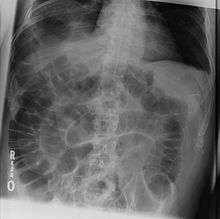

Double wall sign. This is a secondary sign of pneumoperitoneum. Patient is supine, and air within the abdomen and lumen of the bowel accentuate both sides of the bowel wall.

Rigler's sign, also known as the double wall sign, is a radiologic sign seen on an x-ray of the abdomen when air is present on both sides of the intestine; a Rigler's sign is present when air is present on the inside (luminal side) and the outside (peritoneal side). Air in the peritoneum is considered abnormal, unless the patient had a recent abdominal surgery.

A false double wall sign can result from two loops of bowel being in contact with one another.[1]